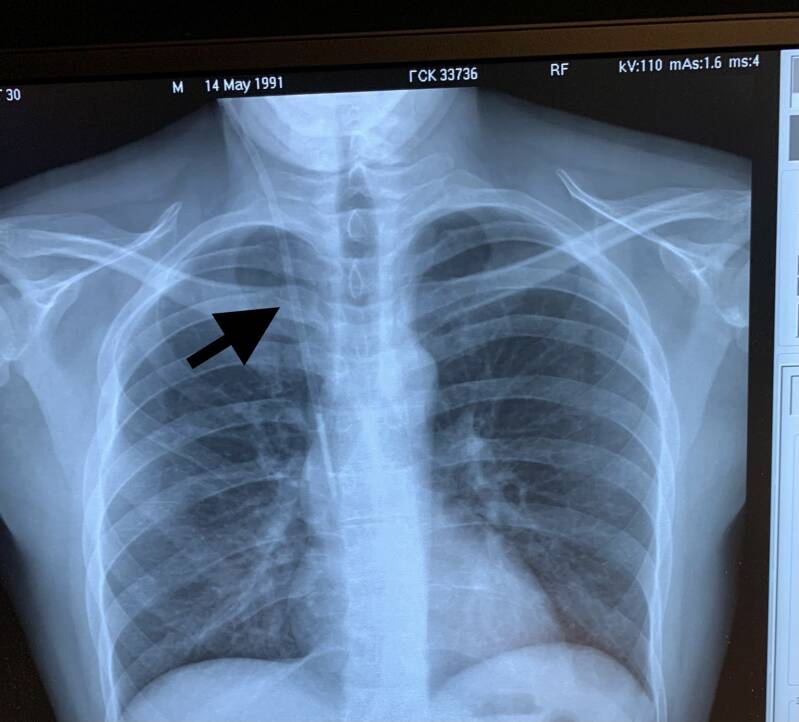

Dinsdagochtend kreeg Bart de neklijn. Dat klinkt vreemd maar dat is een infuus met een behoorlijke doorsnee. Bart vergelijkt het met tuinslang materiaal, of beter gezegd zoals je een rioolput ook doorspuit. Het zou zomaar kunnen dat hij zelf de materialen ook wel in de schuur heeft liggen. De slang gaat via de nek achter de borstkas langs naar het mergbeen. Ongeveer zover tot op hart hoogte. Na het plaatsen werd nog een foto gemaakt om te kijken of het goed geplaatst is. Ja het is gelukt! Hij zit er goed in! Dan nog een dag wachten tot het oogsten van de stamcellen.